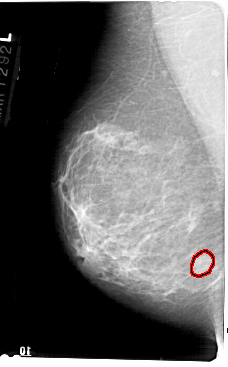

A_1607_1.LEFT_CC

LEFT_CC LINES 5491 PIXELS_PER_LINE 3196 BITS_PER_PIXEL 12 RESOLUTION 43.5 OVERLAY

FILE: A_1607_1.LEFT_CC.OVERLAY

TOTAL_ABNORMALITIES 1

ABNORMALITY 1

LESION_TYPE MASS SHAPE OVAL MARGINS OBSCURED

ASSESSMENT 3

SUBTLETY 2

PATHOLOGY BENIGN

TOTAL_OUTLINES 1

BOUNDARY